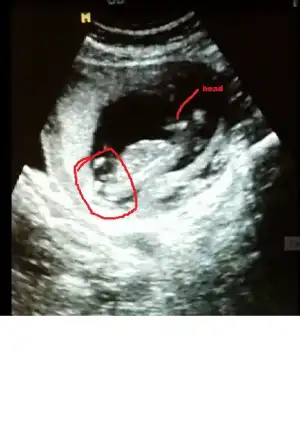

kızlar cinsiyet tahmini yapabilen var mı :)

Gijnij merhaba ben seni ve buranin sıkı takipcilerindenim benim de 2 kizim var ALLAH nasip ederse 3 cuye hamileyim 14 haftalik rica etsem resimi eklesem bana yorum edermisin image.webp